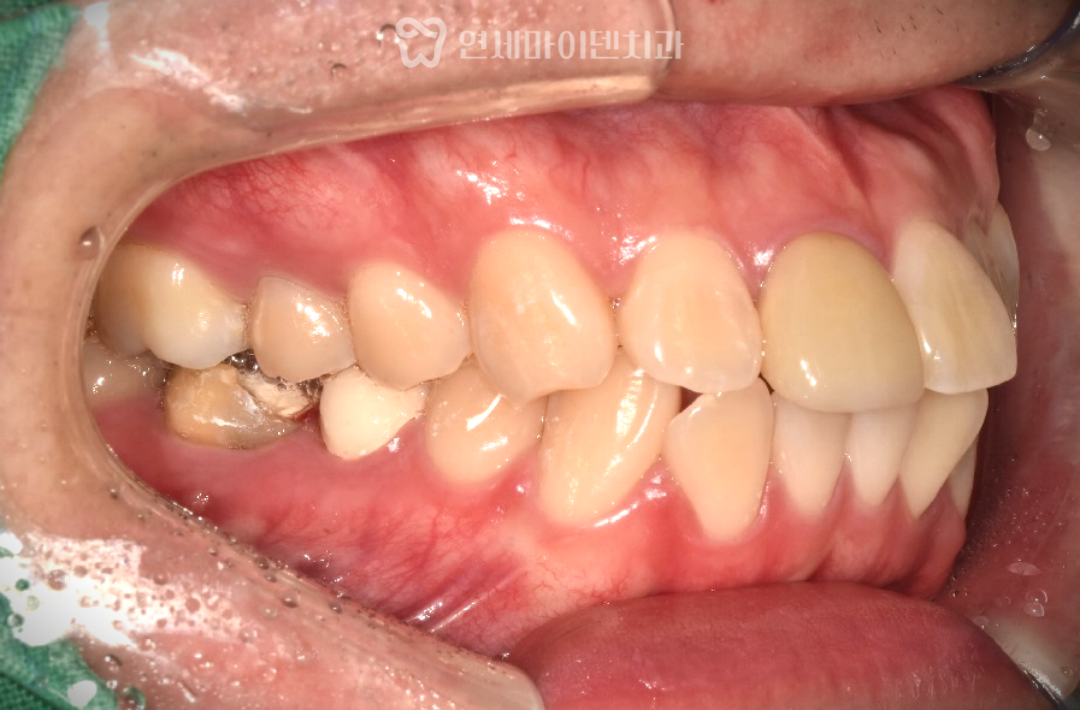

초기 검사 결과,

앞니가 전반적으로 앞으로 뻐드러져 있었고

일부 치아는 신경치료가 불완전하거나

염증이 동반된 상태였습니다.

또한 골격적으로는

위턱이 상대적으로 발달하고

아래턱이 뒤로 들어간

2급 부정교합 양상을 보이고 있었습니다.

이번 케이스는 단순히

돌출입 치열 문제만 있는 상황이 아니라,

몇몇 치아 자체의 예후가 좋지 않았기 때문에

조금 더 신중한 발치 교정 계획이 필요했습니다.

- 신경치료가 불완전하고 예후가 좋지 않은 치아

- 뼈 흡수와 염증 소견이 동반된 치아

이에 따라 오른쪽 아래는 큰어금니(6번),

오른쪽 위와 왼쪽 아래는 5번 치아,

그리고 교합의 대칭을 맞추기 위해

왼쪽 위 역시 5번 치아를 발치했습니다.